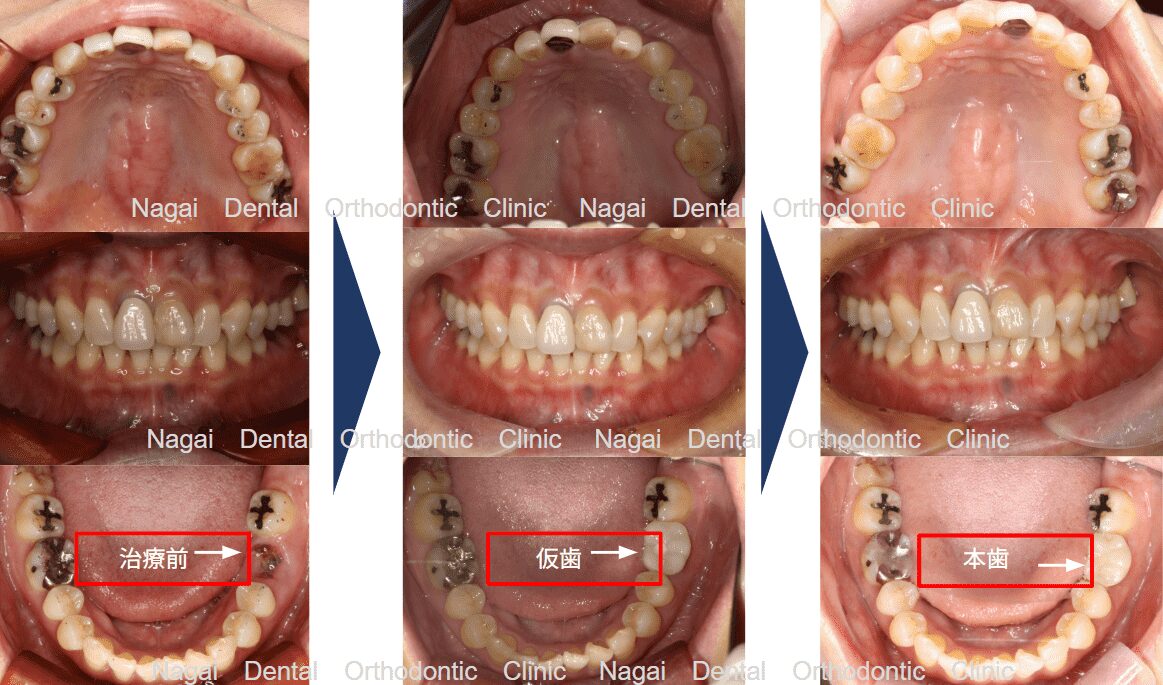

【口腔内の詳細変化】

▲再構築を目的とした治療を行いました

▲支持の安定が期待される治療を行いました

| 治療内容 | 左下顎:インプラント1本 |

|---|---|

| 年齢/性別 | 50代/女性 |

| 背景 | 被せ物の脱離で来院されましたが、精密検査にて保存困難な歯根破折が判明。周囲の健康な歯を削らずに済むインプラント治療を選択し、約4か月で天然歯のような美しさと噛み心地の回復を図りました。審美・機能ともに改善が認められ、再び自信を持って食生活を楽しめるようになっています。 |

| 治療期間 | 約4か月(通院6回) |

| 費用 | 39.6万~49.5万円(税込) |

| リスク/副作用 | インプラント手術は全身状態や持病によっては適応できない場合があります。また、術後の口腔清掃を怠ると、天然歯の歯周病に似たインプラント周囲炎が起こる可能性があるため、定期的なメンテナンスが必要です。 |